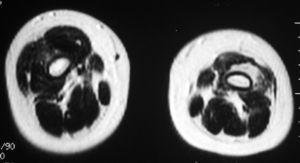

La resonancia magnética (RM) muestra atrofia generalizada de los músculos del compartimento anteroexterno y degeneración lipofibromatosa del vasto intermedio que afecta a todo su trayecto asociándose a una banda fibrosa gruesa que se fusiona con el tendón cuadricipital. Secundariamente, por retracción, apreciamos una posición alta de la rótula con desplazamiento hacia fuera (figs. 2 y 3).

Figura 2. RM de extremidades inferiores, secuencia ponderada en T1, proyección axial, que muestra atrofia generalizada de los músculos del compartimento anteroexterno y degeneración lipofibromatosa del vasto intermedio izquierdo.

Figura 3. RM de extremidades inferiores en proyección coronal, secuencia ponderada en T2 con saturación grasa, donde observamos una banda fibrosa gruesa que se fusiona con el tendón cuadricipital izquierdo, además de posición alta de la rótula con desplazamiento hacia fuera.